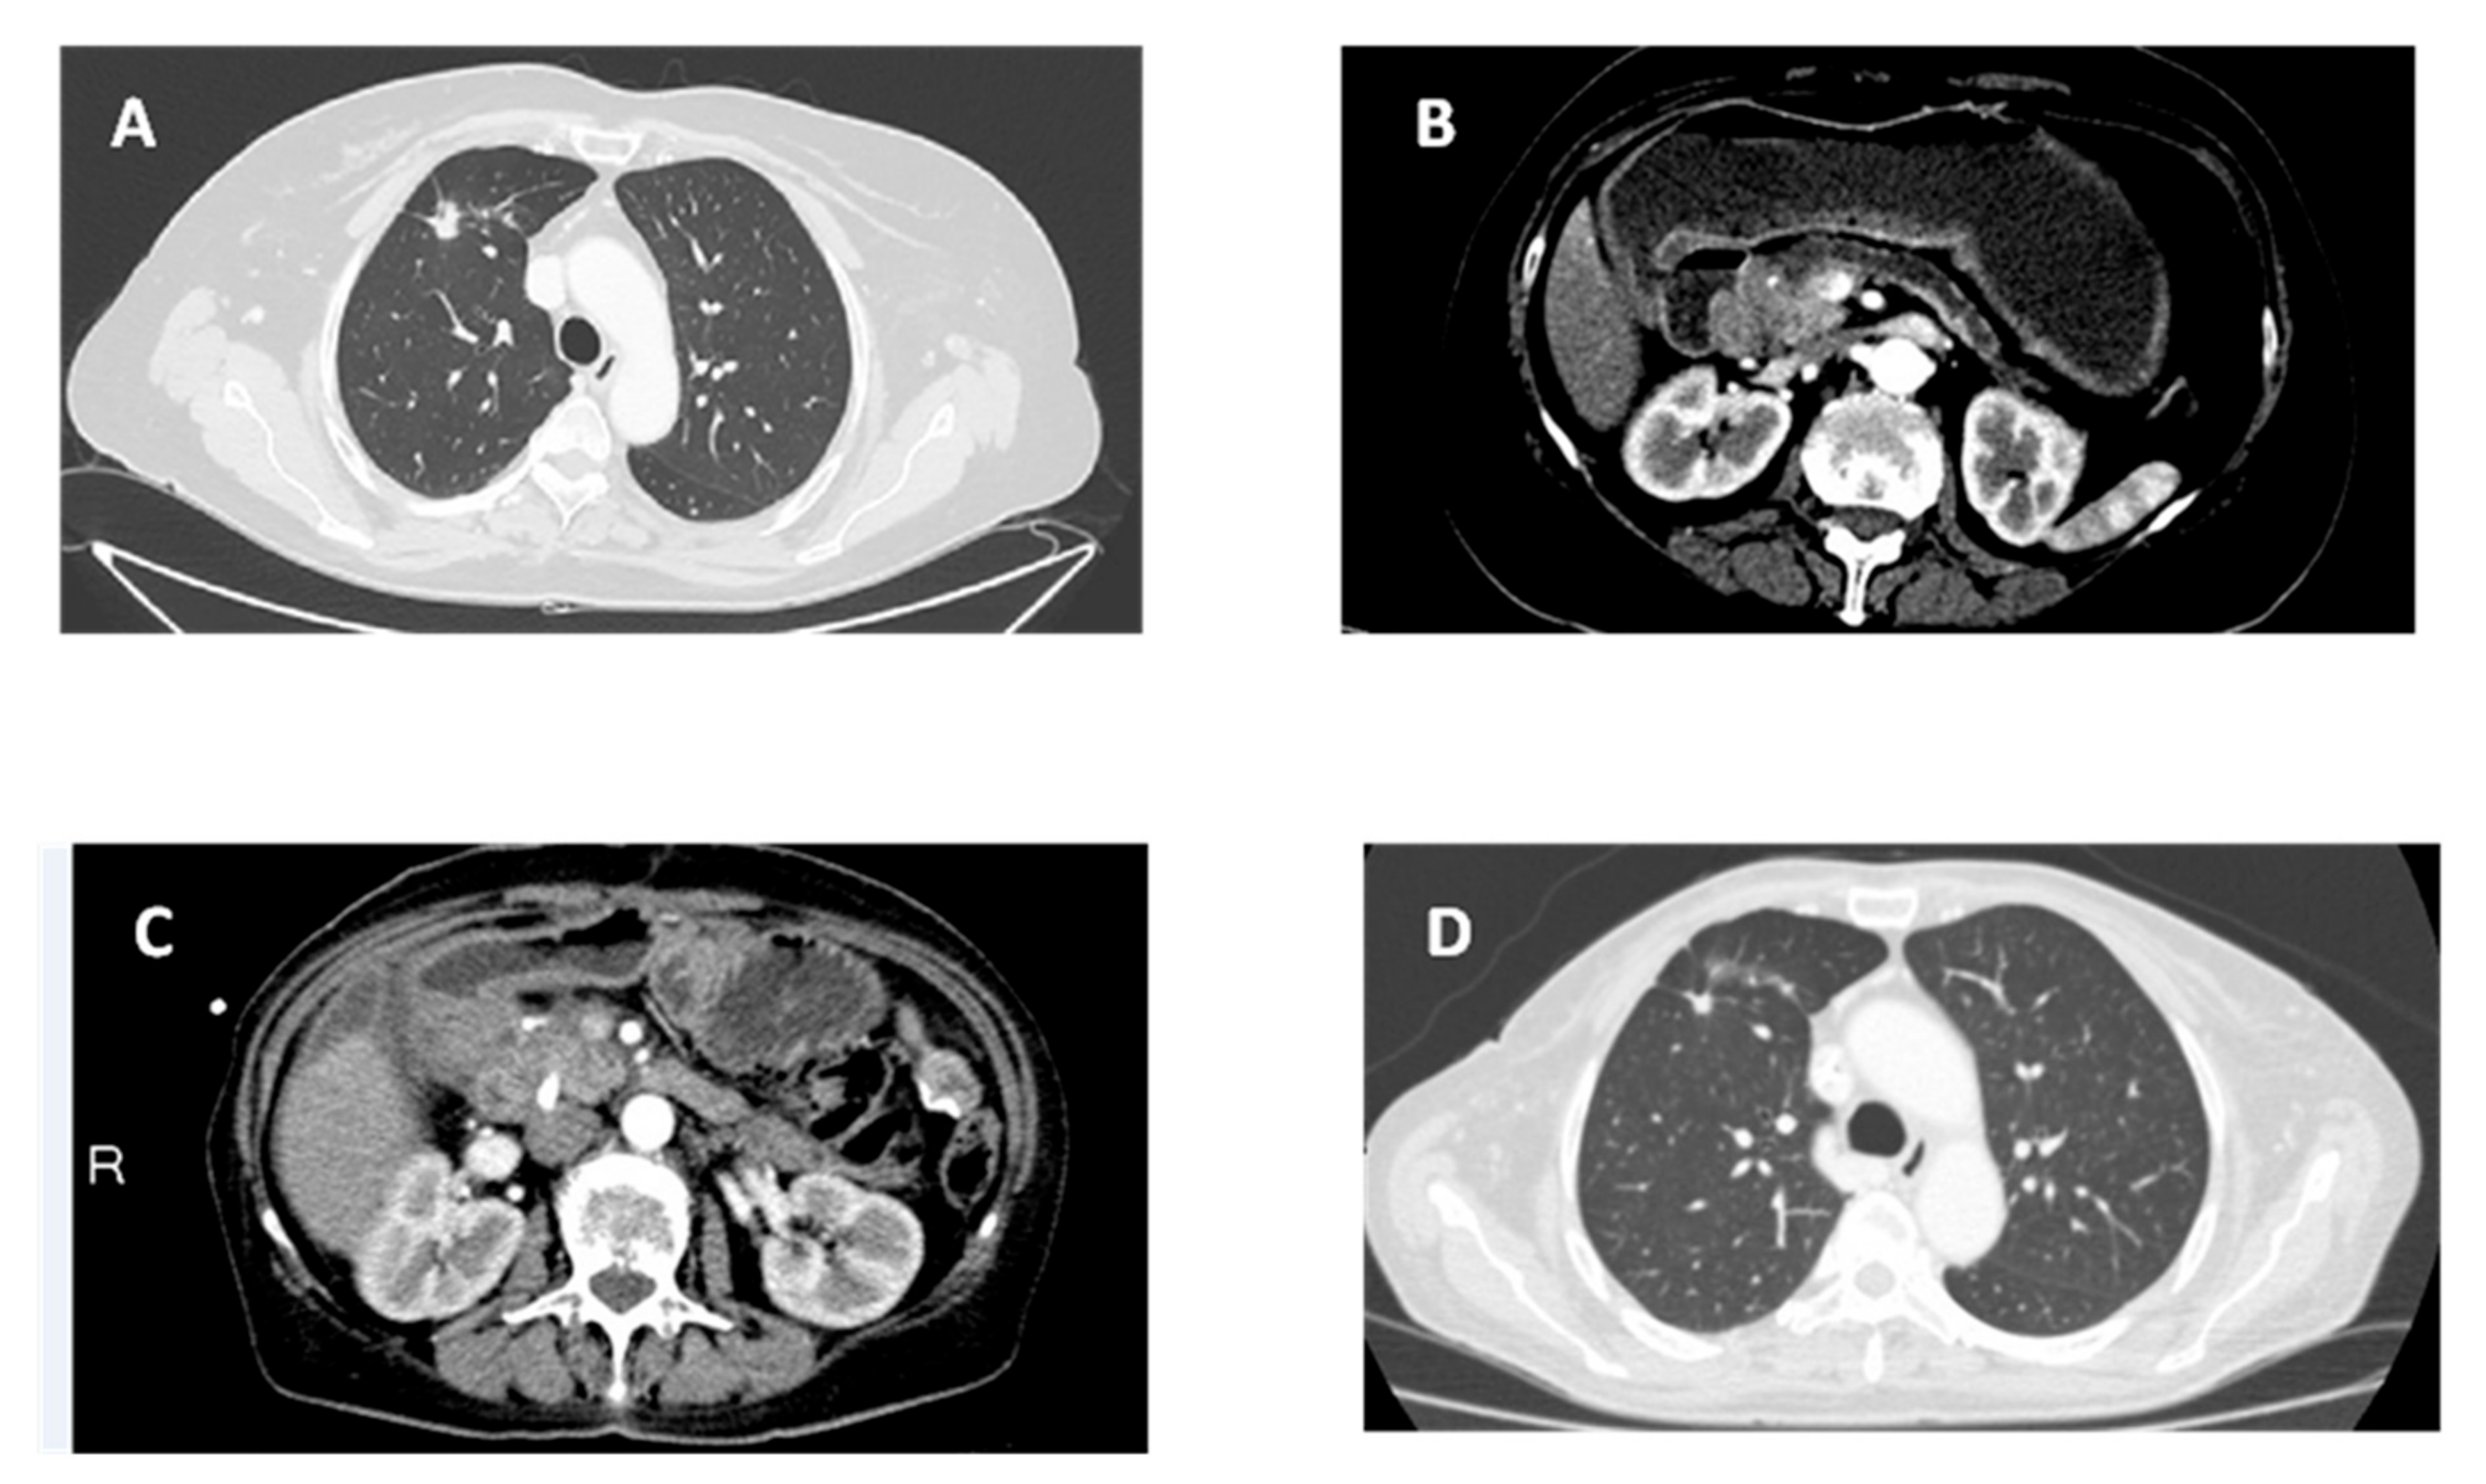

After pericardiocentesis (which resulted positive for cancer cells), the computed tomography scan (CTS) of the chest displayed a nodular opacity (maximum diameter of 1.5 cm with spiculated margins) at the anterior segment of the right upper lobe, suggestive ofa primarylung cancer. An associated parenchymal densification area in the loco-regional area (maximum axial diameter of 2 cm) and other areas of parenchymal densification (diameter ranged from 0.5 to 1 cm) were also present. Two nodular opacities of about 0.3 cm in diameter were evident in the apical segment of the left lower lobe. Moreover, some lymph nodes were described in the hilar-mediastinalarea (maximum short diameter of 0.5 cm) (Figure 1A).

Figure 1. Radiological evaluation of patient with computerized tomography.(A) Radiological presentation of primarylung cancer with pericardial effusion. (B) Radiological presentation of primary pancreatic cancer with bowel obstruction. (C) Radiological presentation of pancreatic cancer at progression. (D) Radiological presentation of primarylung cancer in stable disease.

Eight months later, a CTS of the thorax and abdomen showed duodenal stenosis related to an infiltration by a head-pancreatic mass (Figure 1B). Serum level of CA19.9 was 551 ng/mL. In October 2017, a laparotomy was performed with a gastro-entero anastomosis and multiple biopsies of the visceral peritoneum. Histological examination revealed a moderately differentiated PDAC (cT3N1M1—stage IV) (Figure 2B). Radiological examination confirmed the involvement of the lungs and diaphragmatic lymph nodes in the absence of new parenchymal lesions. The first-line chemotherapy regimen with gemcitabine plus nab-paclitaxel according to von Hoff’s trial [18] with continuation of gefitinib was started. Dose adjustments of both chemotherapeutic drugs were performed according to products’ manufacturing data due to G2 neutropenia toxicity after 4months from the beginning. No dose adjustments were required for gefitinib. This combination therapy resulted to be effective with 13 months of median progression-free survival (PFS)-1 for pancreatic lesion and a partial response as the best radiological response associated with both decreased of Ca 19.9 serum levels (56 ng/mL versus 551 ng/mL) and stability of lung and lymph node lesions.

On November 2018, the onset of hyperbilirubinemia related to the progression of pancreatic lesion required the placement of a biliary endoprosthesis (Figure 1C). At that point, she started second-line chemotherapy with mFOLFOX-6 [19]. Gefitinib administration was continued for the SD of NSCLC (Figure 1D). Again, this combination of systemic chemotherapy with the anti-EGFR TKI resulted well tolerated and effectivewith a radiological stability of pancreatic lesion and lymph node metastases after 20 months. Currently, the patient presents a stable situation for both tumors and she is continuing the combination treatment with PFS of 28 months for NSCLC and an OS and PFS-1 of 20 and 13 months, respectively for PDAC.